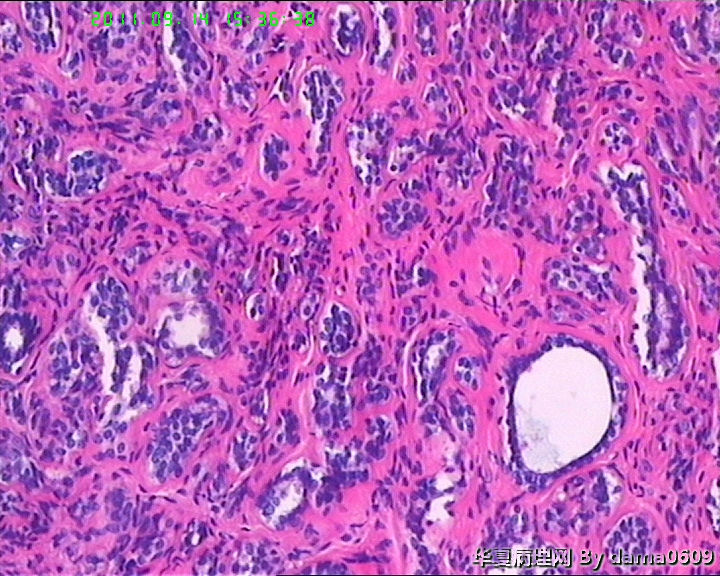

女,22岁,乳腺肿物,病史不详。

不整形软组织肿物一个,V:2.0x1.5x1.5cm。无包膜。切面实性,灰白色,小结节状,质中。

镜下结构复杂,图3、4、8、10、11、12、13、15、17、18、19、20为肿物中央区域,占标本大部分,图1、2、7、14为肿物边缘部分,图5、6、9、16、21为二者交界处。有点乱,不好意思,请老师别介意。

请教老师,诊断:硬化性腺病,可以吗??谢谢!!

• 乳腺肿物,急于求教!!图2

图2

会诊结果::(乳腺)腺管腺病,伴纤维腺瘤形成。

该例患者经上级医院会诊,回报:(乳腺)腺管腺病,伴纤维腺瘤形成。